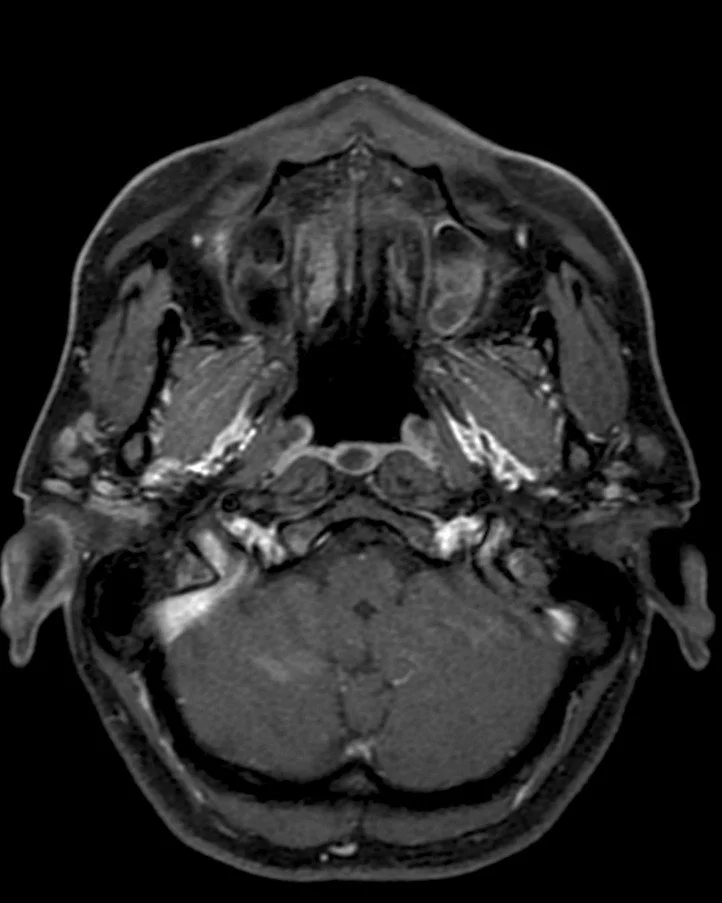

• T1 hypointense, T2 hyperintense, non-enhancing, will restrict diffusion

• Usually seen near mastoid air cells and tympanic membrane